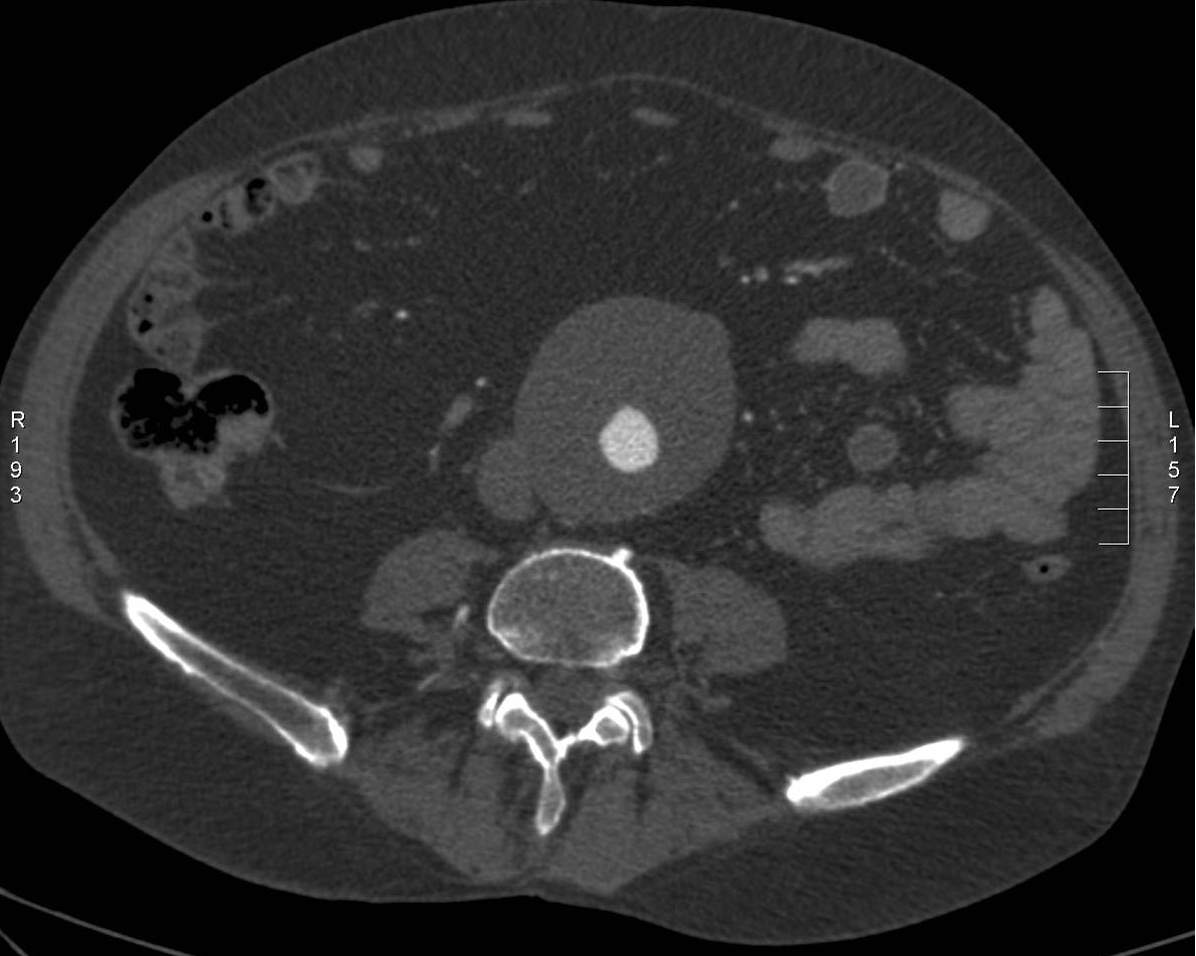

Image

A non-ruptured (stable) aneurysm with an extended mural thrombus

Ruptured aneurysm with retroperitoneal hematoma

Fig. 24., 25.: Abdominal aorta aneurysm, CT angiography